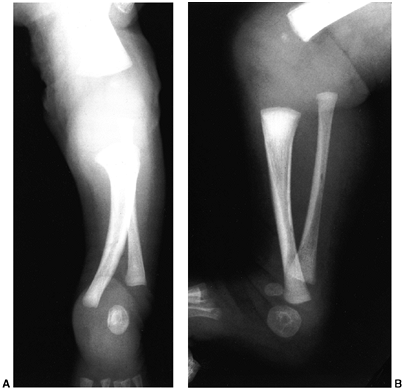

Type II is the absence of the distal tibia, with a proximal portion

that forms a relatively normal articulation with the femur (Fig. 31.7). Type III is distal tibiofibular diastasis (Fig. 31.8).

Figure 31.7 A:

Anteroposterior radiographs of a 4-month-old child with type I tibial deficiency of the right leg and type II deficiency of the left leg. B: On the right leg, he underwent a Brown procedure. Despite the favorable radiographic appearance 4 years after surgery, he developed a severe valgus/flexion deformity, and subsequently had a knee disarticulation on this side. On the left leg, he underwent a synostosis of the fibula to the tibia and a Syme amputation. It is best to excise the proximal remnant of the fibula when performing this procedure, because the continued growth of the proximal fibula produces a large prominence that will interfere with prosthetic fitting. This was resected at the time of his right knee disarticulation. |

Figure 31.8 A, B:

Anteroposterior and lateral views of tibial deficiency of type III of Kalamchi and Dawe, or type 4 of Jones et al. This is sometimes referred to as a diastasis of the ankle mortise. Notice the shortened tibia and the disruption of the normal relation between the tibia and the fibula. |